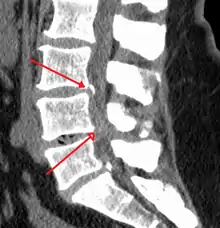

Spinal stenosis is an abnormal narrowing of the spinal canal or neural foramen that results in pressure on the spinal cord or nerve roots.[6] Symptoms may include pain, numbness, or weakness in the arms or legs.[1] Symptoms are typically gradual in onset and improve with leaning forward.[1] Severe symptoms may include loss of bladder control, loss of bowel control, or sexual dysfunction.[1]

Causes may include osteoarthritis, rheumatoid arthritis, spinal tumors, trauma, Paget's disease of the bone, scoliosis, spondylolisthesis, and the genetic condition achondroplasia.[3] It can be classified by the part of the spine affected into cervical, thoracic, and lumbar stenosis.[2] Lumbar stenosis is the most common, followed by cervical stenosis.[2] Diagnosis is generally based on symptoms and medical imaging.[4]

The diagnosis of spinal stenosis involves a complete evaluation of the spine. The process usually begins with a medical history and physical examination. X-ray and MRI scans are typically used to determine the extent and location of the nerve compression.

MRI

MRI has become the most frequently used study to diagnose spinal stenosis. The MRI uses electromagnetic signals to produce images of the spine. MRIs are helpful because they show more structures, including nerves, muscles, and ligaments than seen on X-rays or CT scans. MRIs are helpful in showing exactly what is causing spinal nerve compression.